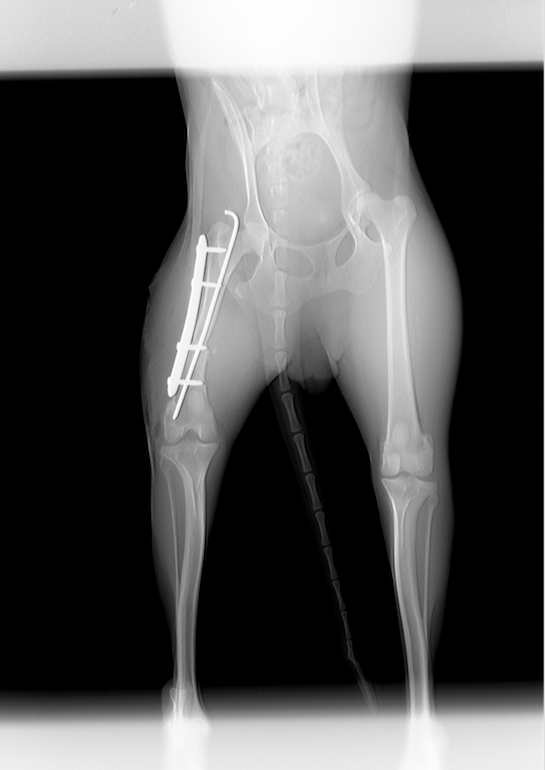

Yuca fué abandonada dejada atada a la puerta de la Protectora, junto a Pomelo. Yuca fractura de femur en su pata trasera derecha, y según los veterianios no es de ahora, llevá así meses, no queremos ni pensar el dolor que ha sufrido durante meses.

La hemos llevado a operar, y a pesar de lo complicada que era, todo ha salido muy bien.